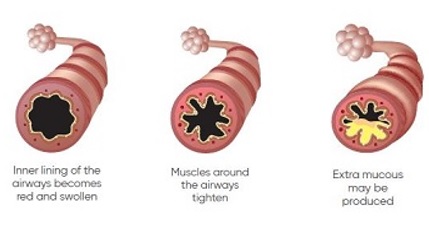

As you breathe, air moves in and out of your lungs through airways or breathing tubes. Each breathing tube has a fine inner lining called a mucous membrane. Wrapped around the airways are muscle fibers that can constrict or relax to alter the size of the airways.

Asthma is a condition of inflammation of the airways caused by certain triggers. With exposure to these triggers, the lining of the airways swell and produces extra mucous . As a result, the muscles tighten and the airways become narrower. This makes it difficult to breathe and results in the condition known as asthma.

As you breathe, air moves in and out of your lungs through airways or breathing tubes. Each breathing tube has a fine inner lining called a mucous membrane. Wrapped around the airways are muscle fibers that can constrict or relax to alter the size of the airways.

Asthma is a condition of inflammation of the airways caused by certain triggers. With exposure to these triggers, the lining of the airways swell and produces extra mucous . As a result, the muscles tighten and the airways become narrower. This makes it difficult to breathe and results in the condition known as asthma.